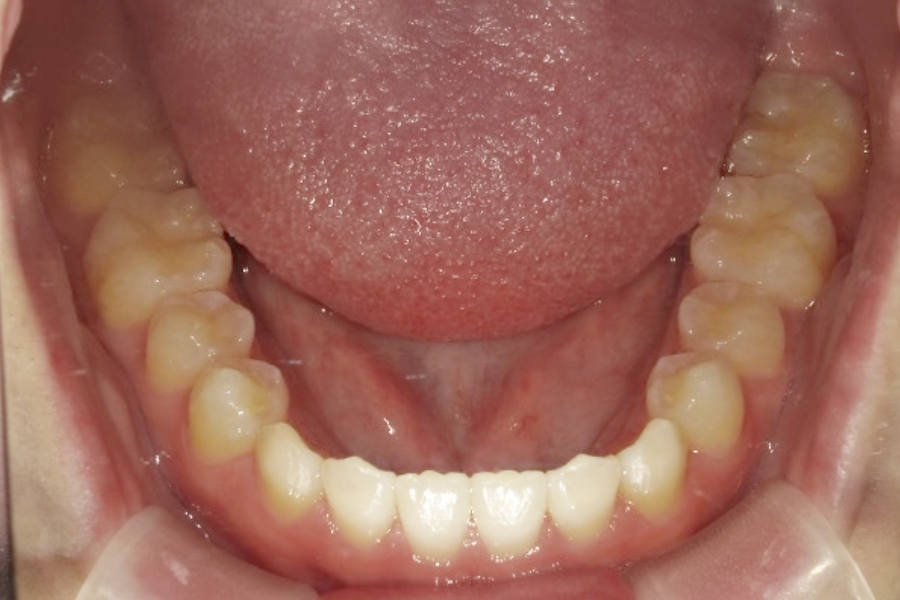

| 主訴 | 前歯のガタガタを治したい |

|---|---|

| 診断名 | 叢生 |

| 年齢 | 22歳 |

| 治療期間 | 2年6ヶ月 |

| 治療費 | 基本料金 ¥990,000 調整料 ¥5,500/月 |

| 治療内容 | 非抜歯 マウスピース型矯正装置 (インビザライン) |

| 治療のリスク | マウスピースの長時間使用が必要、発音への影響、疼痛、歯肉退縮、 歯根吸収 |